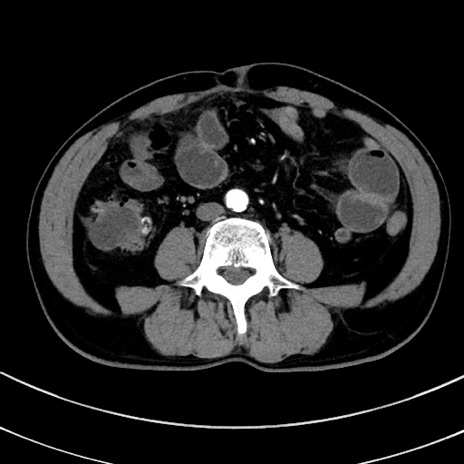

症例8(横断像)

【症例】 60歳代男性

【主訴】 黒色吐物

【現病歴】 4日前から嘔気自覚、2日前の朝食後にも嘔気あり、自分で手で嘔吐反射起こし嘔吐したところ血が混ざっていたため受診。

【既往歴】 5年前汎発性腹膜炎を伴う急性虫垂炎で手術、高血圧、前立腺肥大症、高脂血症

【身体所見】 腹部正中に手術癩痕あり 腹部平坦・軟圧痛なし膨満感あり

【データ】WBC 8400、CRP 4.54